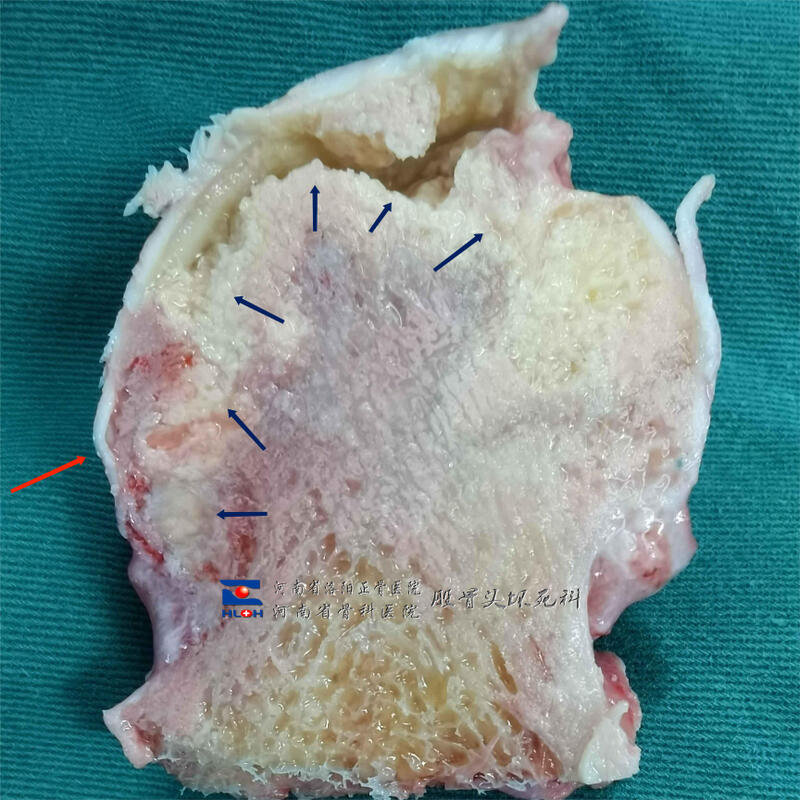

箭头所示区域即为坏死骨,可见坏死骨和软骨下骨已经整体剥离。